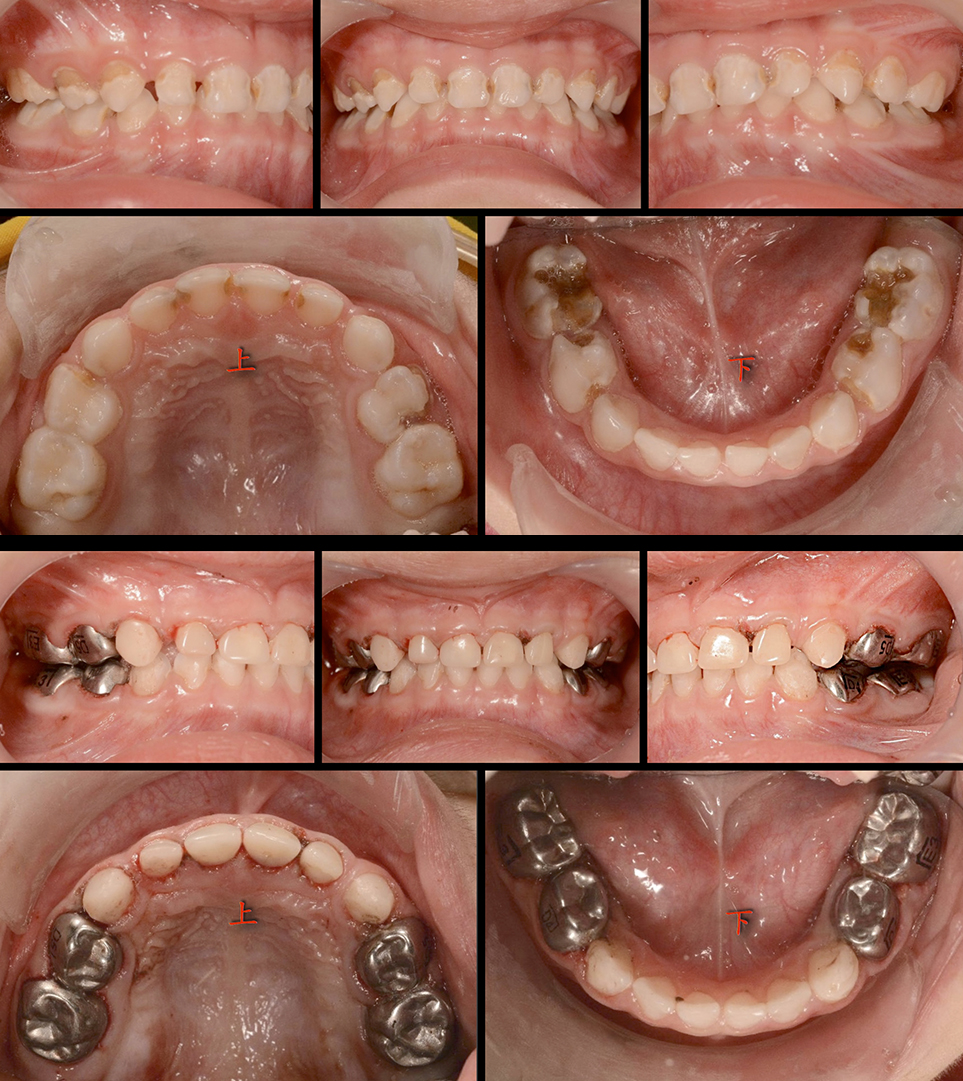

全口齲齒治療-不鏽鋼牙套

感謝匯通牙醫診所提供